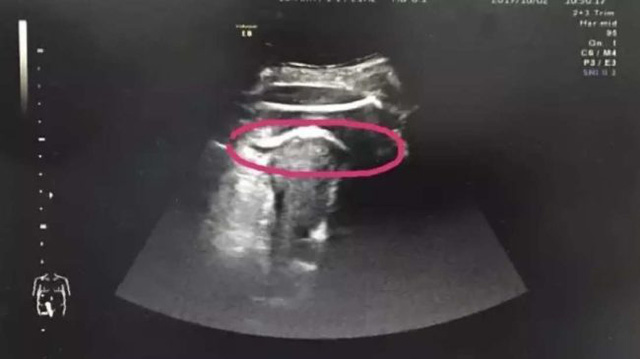

Kết quả siêu âm cho thấy, tử cung bị rách như các bác sỹ phỏng đoán và nguyên nhân do thai nhi 35 tuần tuổi đạp vỡ. Đứa trẻ thậm chí còn thò chân sang khoang bụng khiến đùi bị mắc kẹt ở thành tử cung.